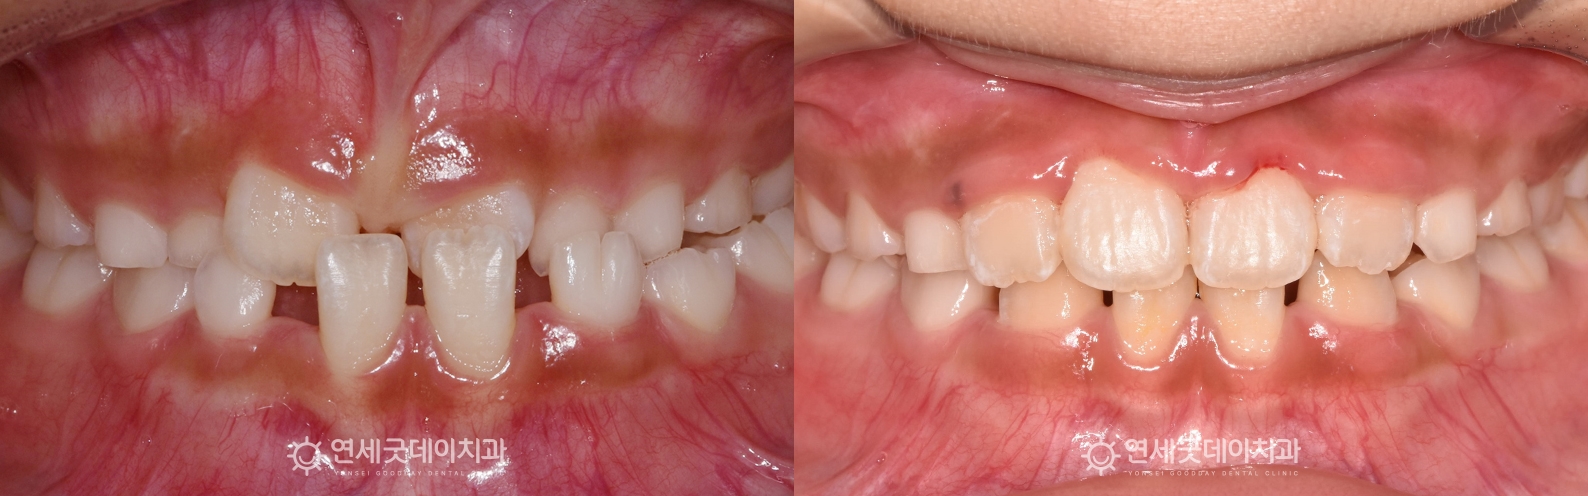

▲ 프리올소 치료전후 비교

약 1년 1개월 간의 성장기치아교정이 잘 마무리되었습니다.

8개월 동안의 프리올소 교정 후 3개월 동안 장치 부분교정을 진행했으며

윗니가 아랫니를 1~2mm 정도 덮는 정상교합으로 개선되었습니다.

성장기치아교정은 치아배열과 교합을 바로 잡아줌으로써

균형잡힌 얼굴 성장을 유도하고, 보다 짧은 치료기간 내 교정 효과를 극대화 시킬 수 있습니다.